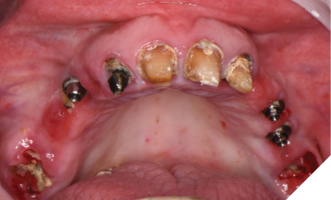

A 55-year-old woman presented with a chief complaint of wanting to complete the treatment of her maxilla and mandible that had begun elsewhere a number of years ago. The patient reported that she had several implants placed and provisional bridges inserted a number of years ago. A review of her medical history revealed no significant findings. A clinical exam was performed, and the following data was collected: a full mouth series radiographic survey, a cone beam CT scan, intraoral surfaces scans, full face and intraoral photos (Figs. 1,2,3).

All teeth and implants were evaluated, and it was determined that due to their poor and compromised prognosis that fully implant supported fixed prosthesis would be the treatment of choice and that all the patient’s remaining teeth would be extracted. The patient had 1 maxillary implant that was to be retained due to its favorable prognosis. All other maxillary implants and mandibular implants exhibited significant bone loss and were to be removed.

Treatment phase: The patient requested that we treat the maxilla first followed by the mandible. The surgical visit included the following treatment. Extraction of teeth 2,7,8,9,15 and removal of implants 5 and 13. Implant 14 was kept due to its good bone support and favorable prognosis (Figs. 6A, 6B). Computer guided surgery (Keystone – Contra Angle Guidance System) with a surgical guide was utilized to perform all osteotomies and place the dental implants (Figs. 7A, 7B).

Fig. 6A

Fig. 6B